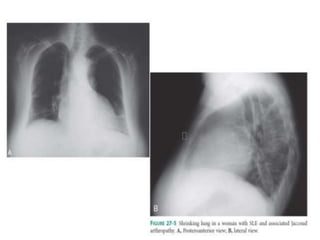

PULMONARY MANIFESTATION

• PLEURITIS with or without pleural effusion.

• When Mild, may respond to treatment NSAIDs

• When More Severe, patients require glucocorticoid

therapy.

• Pulmonary Infiltrates also occur as a manifestation of

active SLE

• Life-threatening pulmonary manifestations include

interstitial inflammation leading to fibrosis, shrinking

lung syndrome, and intraalveolar hemorrhage

PULMONARY MANIFESTATION • PLEURITISwith or without pleural effusion. • When Mild, may respond to treatment NSAIDs • When More Severe, patients require glucocorticoid therapy. • Pulmonary Infiltrates also occur as a manifestation of active SLE • Life-threatening pulmonary manifestations include interstitial inflammation leading to fibrosis, shrinking lung syndrome, and intraalveolar hemorrhage